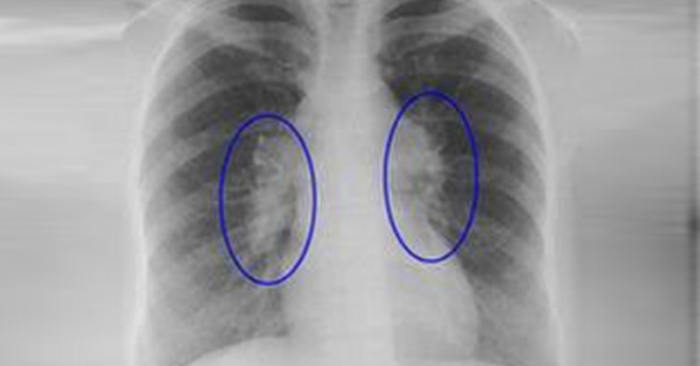

Sarkoidoz - səbəbi tam məlum olmayan, orqanizmdə iltihabi hüceyrələrin toplanması ilə xarakterizə olunan sistem xəstəliyidir.

Bakıvaxtı.az-ın xəbərinə görə, araşdırmalar göstərir ki, bu xəstəlik zamanı müxtəlif orqanlarda “qranuloma” adlanan kiçik iltihabi düyünlər əmələ gəlir. Sarkoidoz ən çox ağciyərləri və limfa düyünlərini zədələsə də, gözlər, dəri, ürək və digər orqanlara da təsir göstərə bilər.

Diaqnoz qoyulması üçün həkimlər bir neçə üsuldan istifadə edir. Əsasən rentgen və ya kompüter tomoqrafiyası ilə ağciyərlər müayinə olunur, qan analizləri aparılır və dəqiq təsdiq üçün biopsiya ilə toxuma nümunəsi götürülür.